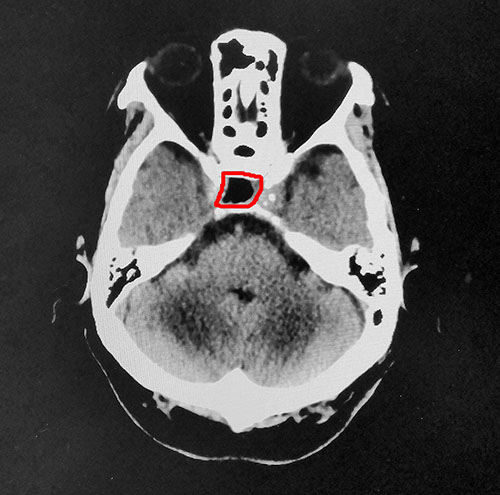

▲術后CT影像:腫瘤切除干凈,鞍內腦脊液填充

整個切除手術用時不到1小時,術中出血量很少,腫瘤切除干凈。術后王老伯被醫(yī)護人員喚醒,被安全送到重癥監(jiān)護室監(jiān)護。